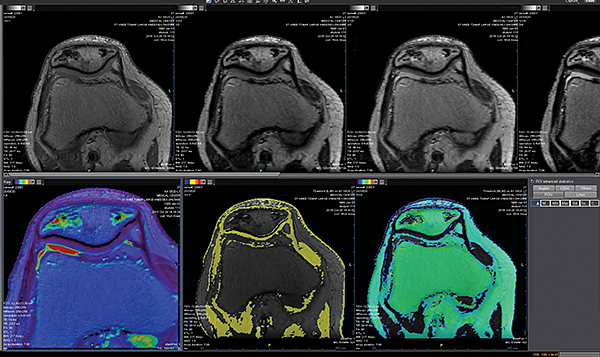

Додаток Head and Neck Streamlined.

Додаток Head and Neck забезпечує автоматичну оцінку дифузії, розрахунок карт проникності для контрасту, включаючи кількісні дані для ефективної оцінки відповіді пацієнта на лікування.